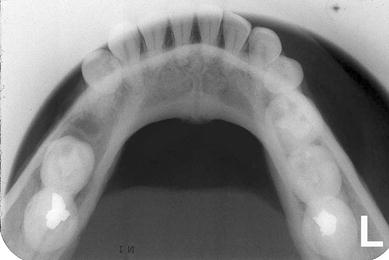

A 42-year-old Caucasian female presented with extreme pain of the right mandible and paresthesia of her right lower lip from the commissure to the midline. The patient reported that sudden severe pain began 4 months earlier in the right mandible. Consultation with a private dentist for the pain resulted in the initiation of endodontic therapy for tooth #30. Subsequent to the completion of root canal treatment on tooth #30, the pain increased and the paresthesia began. Both the pain and paresthesia were non-responsive to a short course of steroids and antibiotics. Tooth #30 was extracted 1 month prior to presentation. Following the extraction, the pain and paresthesia worsened and a “swishing” sound developed in her right ear. Evaluation by otolaryngology was negative. Intraoral and extraoral examinations were unremarkable except for the right lower lip paresthesia. Panoramic (Fig. 1), occlusal (Fig. 2) and periapical radiographs (Fig. 3) were taken at the time of presentation.

Fig. 2

Occlusal radiograph